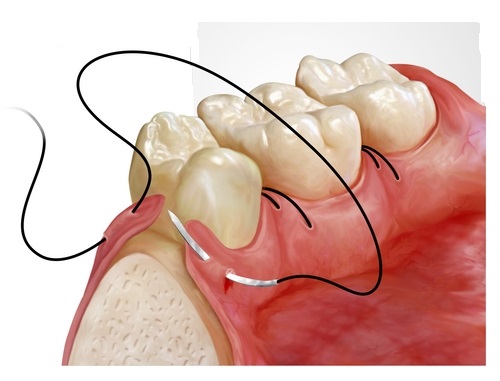

Gömülü 20 yaş dişi çektirmek şart mı?

Tüm gömülü 20 yaş dişlerinin çekilmesi gerekmez. Ağrı, enfeksiyon, kist, komşu diş üzerinde baskı yapma veya ortodontik tedavi gerekliliği varsa çekilmelidir. Semptom vermeyen ve doğru pozisyondaki 20 yaş dişleri takip edilebilir. Diş hekiminiz röntgen sonucu karar verecektir.

Gömülü diş operasyonu ne kadar sürer?

Basit gömülü diş çekimleri 20-30 dakika, karmaşık vakalar 45-60 dakika sürebilir. İşlem lokal anestezi altında yapılır. Gerekirse sedasyon veya genel anestezi de uygulanabilir. İyileşme süreci 7-10 gündür, dikişler 7. günde alınır.